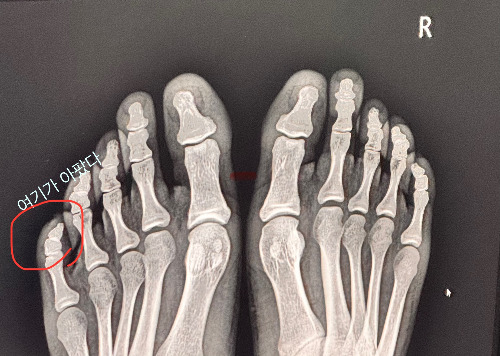

최근, 발가락을 문지방에 찧었다. 내가 힘차게 걷는다는 것을 이번 기회에 새로 알았다. 마침 배가 너무나 고팠던 탓에 나온 조급한 발걸음이 화근이었던 것이다. 부딪힌 순간 옆으로 쓰러졌고 비명을 질렀다. 하지만 너무 아프고 배도 고팠기에 비명소리는 처참히 공기반 소리반으로 나왔다. 마치 기름칠 안한 문짝이 열고 닫히는 소리처럼말이다. 비참했지만 위로해줄 사람도 없었기에 꾹 참고 밥도 먹고 운동도 다녀왔다.

나는 나름 문지방과 여러번 싸워 본 경험자이기때문에 이번에도 대수롭지않게 생활을 이어갔다. 역시나 붓고 멍이 들더니 이내 통증이 사라졌다. 역시 놔두면 났는다니까! 하며 매일 테이핑을 붙이고 스파링도 이어나갔다. 그러다 일주일이 되던 날 예사롭지 않은 고통이 느껴졌다.

너무 아파! 하는 것보다 오 좀 아픈걸 ? 하하 이런 아픔이 진짜 큰일난 것이라는 걸 아는가? 나는 정확히 후자였고 역시나 의사선생님께 발가락을 2주 압수 당했다. 적당한 상태면 자기시간치료법을 쓰려고 했는데 초음파를 보고 조용히 입을 다물수밖에 없었다. 지난 일주일동안 아픈 새끼(발가락)를 옆 약지친구한테 묶어서 소생시켰는데 그것이 더 큰 문제였던 것 같다.

사실 나는 발도 작지만 발가락, 특히 새끼 발가락은 더 작아서 이 작은 발가락에 테이핑을 감는 것이 조금 웃기다고 생각했다. 그래서 안일하게 여겼는데 이번 기회에 이 새끼(발가락)의 존재감을 확실히 느끼게 되었다.